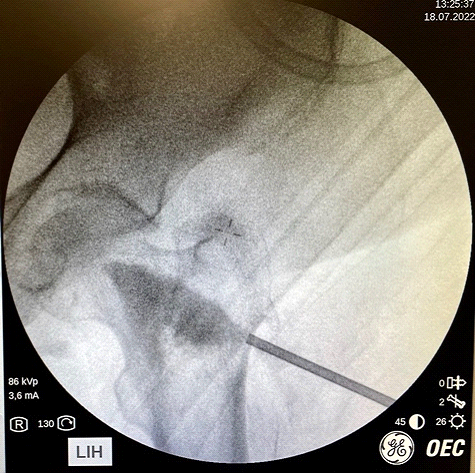

Actualmente tenemos la posibilidad de mejorar la resistencia del hueso y prevenir las fracturas de las personas mayores. Lo hacemos con una simple inyección dentro del hueso de una sustancia cálcica especial (OSSURE LOEP) que le fortalece y estimula la regeneración del hueso propio. Este efecto es inmediato, a diferencia de la medicación, que tarda meses o años en conseguirlo.

El producto OSSURETM LOEP se INYECTA EN EL HUESO para RELLENAR Y formar hueso nuevo en áreas del esqueleto OSTEOPOROTICO QUE PRESENTA MULTIPLES PEQUEÑAS CAVIDADES VACIAS. ESTE material biorreabsorbible, Y osteoconductor ESTÁ HECHO A BASE DE CALCIO. El procedimiento de mejora ósea local es un procedimiento mínimamente invasivo. Se inyecta en sitios preparados quirúrgicamente OSSURE donde se endurece, se reabsorbe y se reemplaza con hueso nuevo.

El procedimiento suele durar menos de 30 minutos.